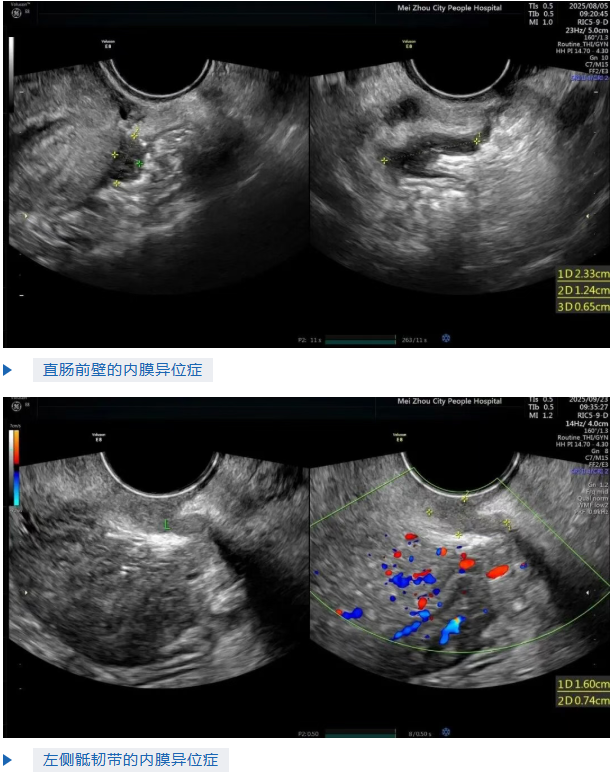

这些情况,都可能是深部浸润型子宫内膜异位症引起的。它很会“伪装”,但通过专门的超声检查,就能把它找出来。

通俗点说,“深部浸润型子宫内膜异位症”就是:本该乖乖待在子宫里的内膜细胞, 不知为何 “跑偏”了,钻到了盆腔深处。它们在一些本不该出现的地方“赖着不走”,比如子宫附近的韧带、直肠或膀胱。这些“非法定居”的细胞,每次来月经时也会出血,但这些血根本排不出去。于是,它们就在身体里“搞破坏”,慢慢形成病灶,不断刺激和损害周围的组织。正因如此,它不仅会引起各种疼痛,还会干扰生殖系统的正常功能,导致怀孕变得非常困难。

精准定位:它的精准度更是没话说,就像“透视眼”那样,能帮医生迅速定位病灶,明确病情,给后续治疗提供精准方向。